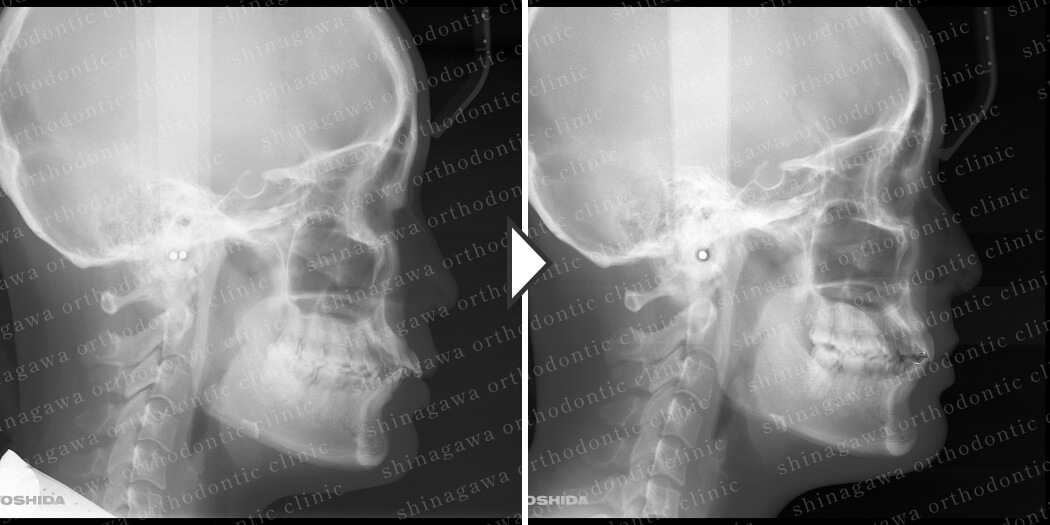

症例3

下顎前突

| 年齢 | 34 歳 |

|---|---|

| 性別 | 女性 |

| 住所 | 東京都目黒区 |

| 主訴 | 出っ歯 |

| 不正咬合の種類(診断) | 下顎前突 |

| 装置 | 表ワイヤー |

| 抜歯/非抜歯 | UR4, UL4 |

| 期間 | 24M |

| 費用 | 935,000 円 |

| リスク・副作用 | 矯正治療による歯の移動に伴う痛み, 虫歯, 歯肉退縮, 歯根吸収 |